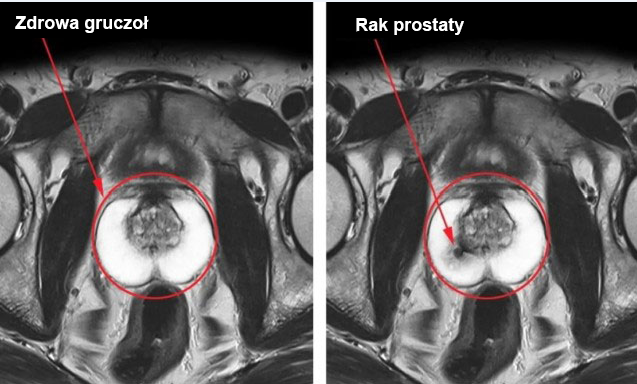

Problemy z prostatą: zapalenie gruczołu krokowego, przerost prostaty, a w niektórych przypadkach zwiększone ryzyko raka prostaty w ciągu 3-4 lat. |

Chroni prostatę i zapobiega problemom z gruczołem krokowym

Większość problemów z prostatą u mężczyzn wiąże się z zastojem płynu nasiennego. Ponieważ Shiitake Premium przywraca aktywne życie seksualne, pomaga również wyeliminować ten problem. Co więcej, jego formuła zawiera wiele aktywnych składników, które mają pozytywny wpływ na tkanki prostaty. Dlatego nie tylko wspiera potencję, ale także poprawia zdrowie prostaty i może zapobiegać powikłaniom, takim jak przerost prostaty.

Rak prostaty może rozwinąć się u mężczyzn z zaburzeniami erekcji w ciągu 8-12 lat. Najlepszym sposobem na zmniejszenie tego ryzyka jest utrzymanie aktywnego życia seksualnego do późnej starości, najlepiej nawet po 80 roku życia.

Rak prostaty może rozwinąć się u mężczyzn z zaburzeniami erekcji w ciągu 8-12 lat. Najlepszym sposobem na zmniejszenie tego ryzyka jest utrzymanie aktywnego życia seksualnego do późnej starości, najlepiej nawet po 80 roku życia. Wzmacnia układ sercowo-naczyniowy